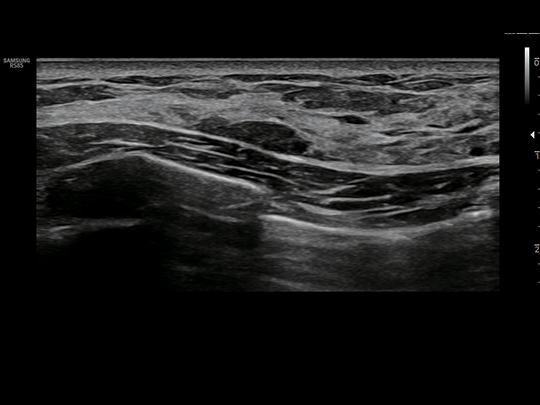

WideScreen provides approximately 23% more lateral viewing information compared to normal screen, allowing ultrasonic examination with wider view at a glance.